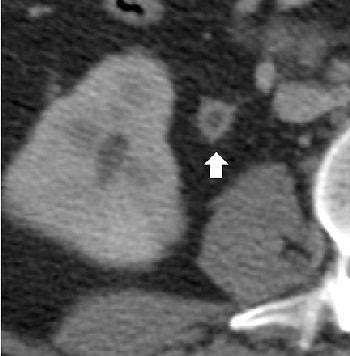

![]() |

| Image A. Contrast-enhanced nephrographic-phase CT scan shows dilated calices and thinning of the renal cortex (arrow). |

With conventional radiography, renal calcifications are a common manifestation of tuberculosis occurring in 25% to 44% of patients. CT is useful in determining the extent of renal and extra renal spread of the disease. Coalesced cortical granulomas and parenchymal scarring is apparent at CT, while fibrotic structures of the renal pelvis and ureters may be seen on contrast-enhanced CT, suggesting tuberculous infection.

| Image B. Magnified view from a contrast-enhanced nephrographic-phase CT scan, obtained caudad to image A, shows mural enhancement and thickening of the proximal ureter (arrow). Figures 2a, b, Gibson MS, Puckett ML, Shelly ME, "Renal Tuberculosis," (RadioGraphics 2004; 24: 251-256). |